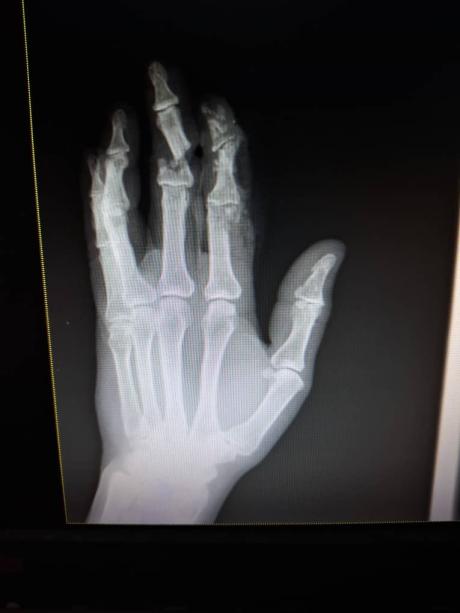

X-ray scan of of Israel's hand

“I was rushed to Totokea hospital,” Israel said. “They cared for me promptly. The surgery went on for about three hours to reattach my index finger.”

“My middle finger was severed completely and therefore it was not possible to save it,” he said.